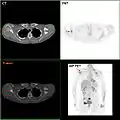

MRI showing breast cancer

Micrograph showing a lymph node invaded by ductal breast carcinoma, with an extension of the tumor beyond the lymph node

F-18 FDG PET/CT: A breast cancer metastasis to the right scapula